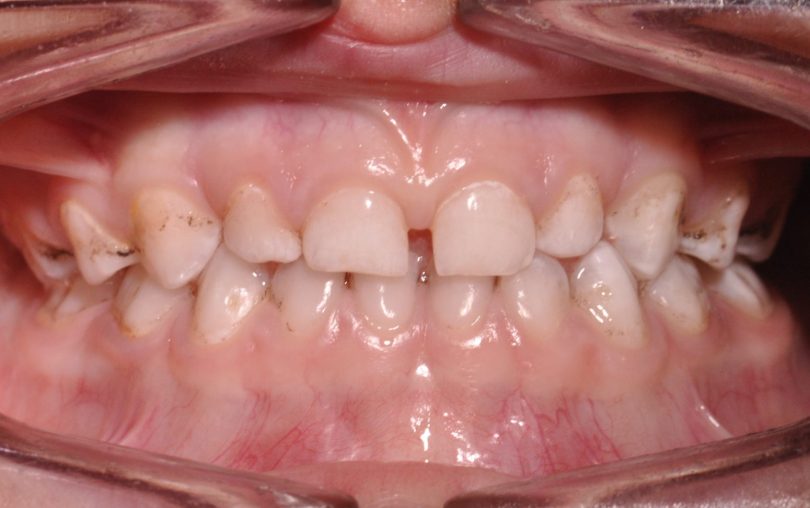

Foi realizado um exame clínico e radiológico inicial (fig. 1 a 3), tendo sido diagnosticada, entre outras lesões de cárie, uma lesão de cárie profunda com atingimento pulpar no segundo molar temporário inferior direito (fig. 3). Foi proposta a realização de uma pulpotomia com agregado trióxido mineral (MTA) e a colocação de uma coroa pré-formada. As várias possibilidades restauradoras foram apresentadas e discutidas com os pais, que decidiram optar pela colocação de uma coroa pré-formada de zircónia, por motivos estéticos.

Foi também sugerida a realização de sedação consciente devido à história prévia de falta de colaboração do paciente, tendo sido também aceite pelos responsáveis o recurso a esta técnica de controlo de comportamento, o que possibilitou a execução do plano de tratamento estipulado (fig. 4).

A realização de tratamentos com alguma complexidade em crianças pouco colaborantes implica, por vezes, o recurso a técnicas de controlo de comportamento, como a sedação consciente com protóxido de azoto. No caso clínico apresentado, de um paciente com história prévia de incapacidade de colaboração, o recurso à técnica de sedação consciente possibilitou a realização de uma pulpotomia com ajuste de uma coroa de zircónica no dente 85 e da restauração distal do dente 84, numa só sessão.